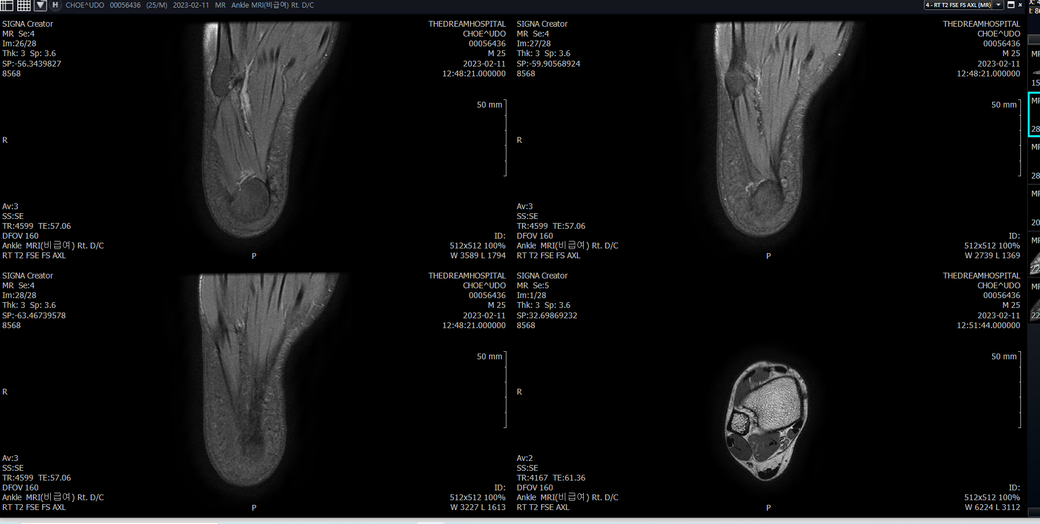

우선 전반적으로 봤을 때 큰 이상은 없어보입니다.

전거비인대 등도 저명한 손상은 없는 것 같아 보이지만, 어느 부분의 통증 등으로 인해 촬영을 하셨는지 말씀을 해주신다면 보다 정확한 병변파악이 가능하겠으며, 병원에서 판독이 완료되신다면 전화 등으로 문의를 해보시는 것이 좋겠습니다.